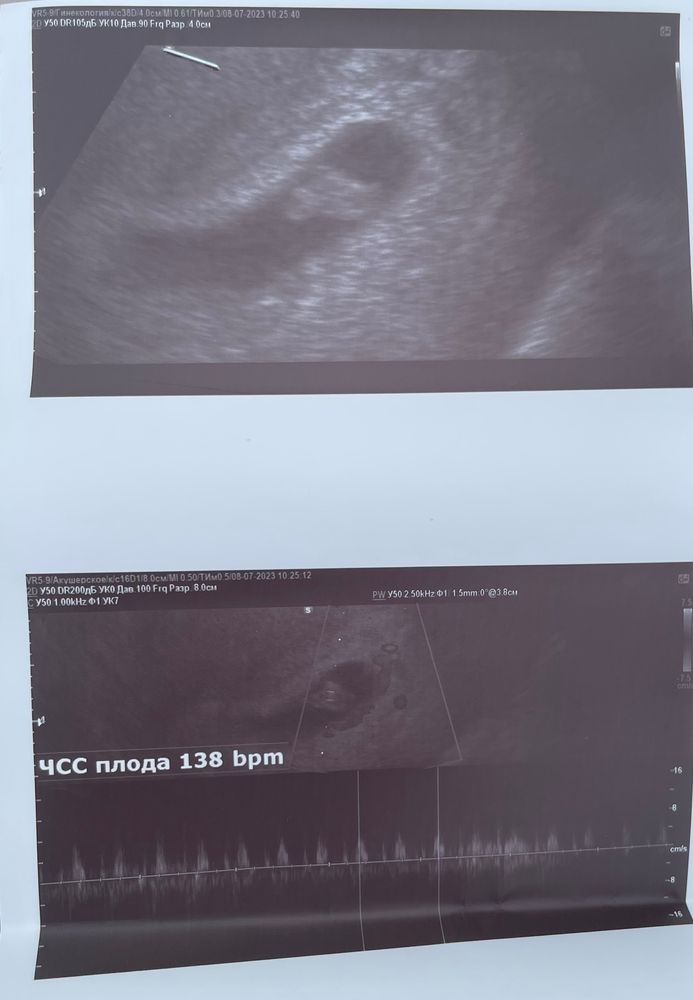

Подскажите,пожалуйста,вытянутое плодное яйцо.Гинеколог сказала,что небольшой тонус и прописала папаверин через день свечи.

у меня на скрининге в 13 недель тоже неровное было, возможно просто такое фото!) когда водили датчиком, оно было то ровное, то кривое, непонятное в общем. а если тонус говорит, так точно в пределах нормы

У меня тоже неровное плодное яйцо было, но врач ничего не сказал, тонуса не было.